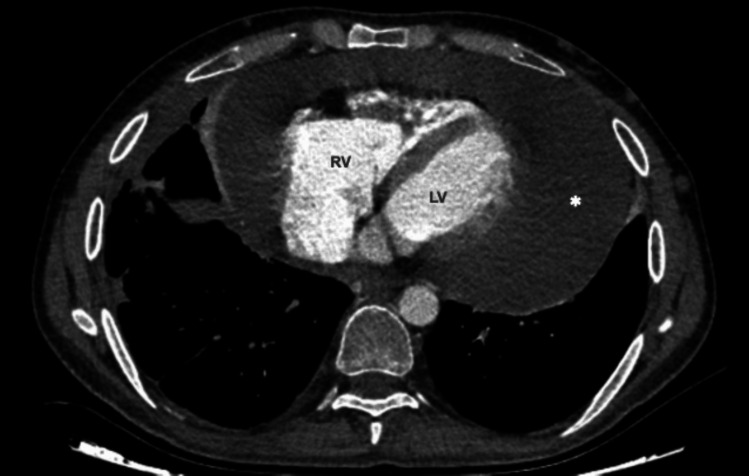

Purpose of the review: Behçet's Syndrome (BS) is a multisystemic vasculitis that can affect the heart, leading to pericarditis, myocarditis, intracardiac thrombosis, endomyocardial fibrosis, valvular dysfunction, and coronary artery disease. This review summarizes the clinical presentation, diagnostic challenges, and therapeutic strategies for cardiac involvement in BS.

Recent findings: Advanced imaging techniques have revealed subclinical cardiac involvement in BS. Myocardial dysfunction and fibrosis contribute to heart failure and arrhythmias, while intracardiac thrombi often coexist with pulmonary artery involvement. Coronary artery vasculitis and aneurysms may mimic atherosclerotic disease, complicating diagnosis. Biologic therapies, including TNF-α inhibitors, show promise in refractory cases. Early diagnosis and immunosuppressive therapy are crucial. A multidisciplinary approach is essential to managing cardiac complications and optimizing patient outcomes. Future research should refine screening protocols and explore targeted immunotherapies for BS-related cardiovascular disease.